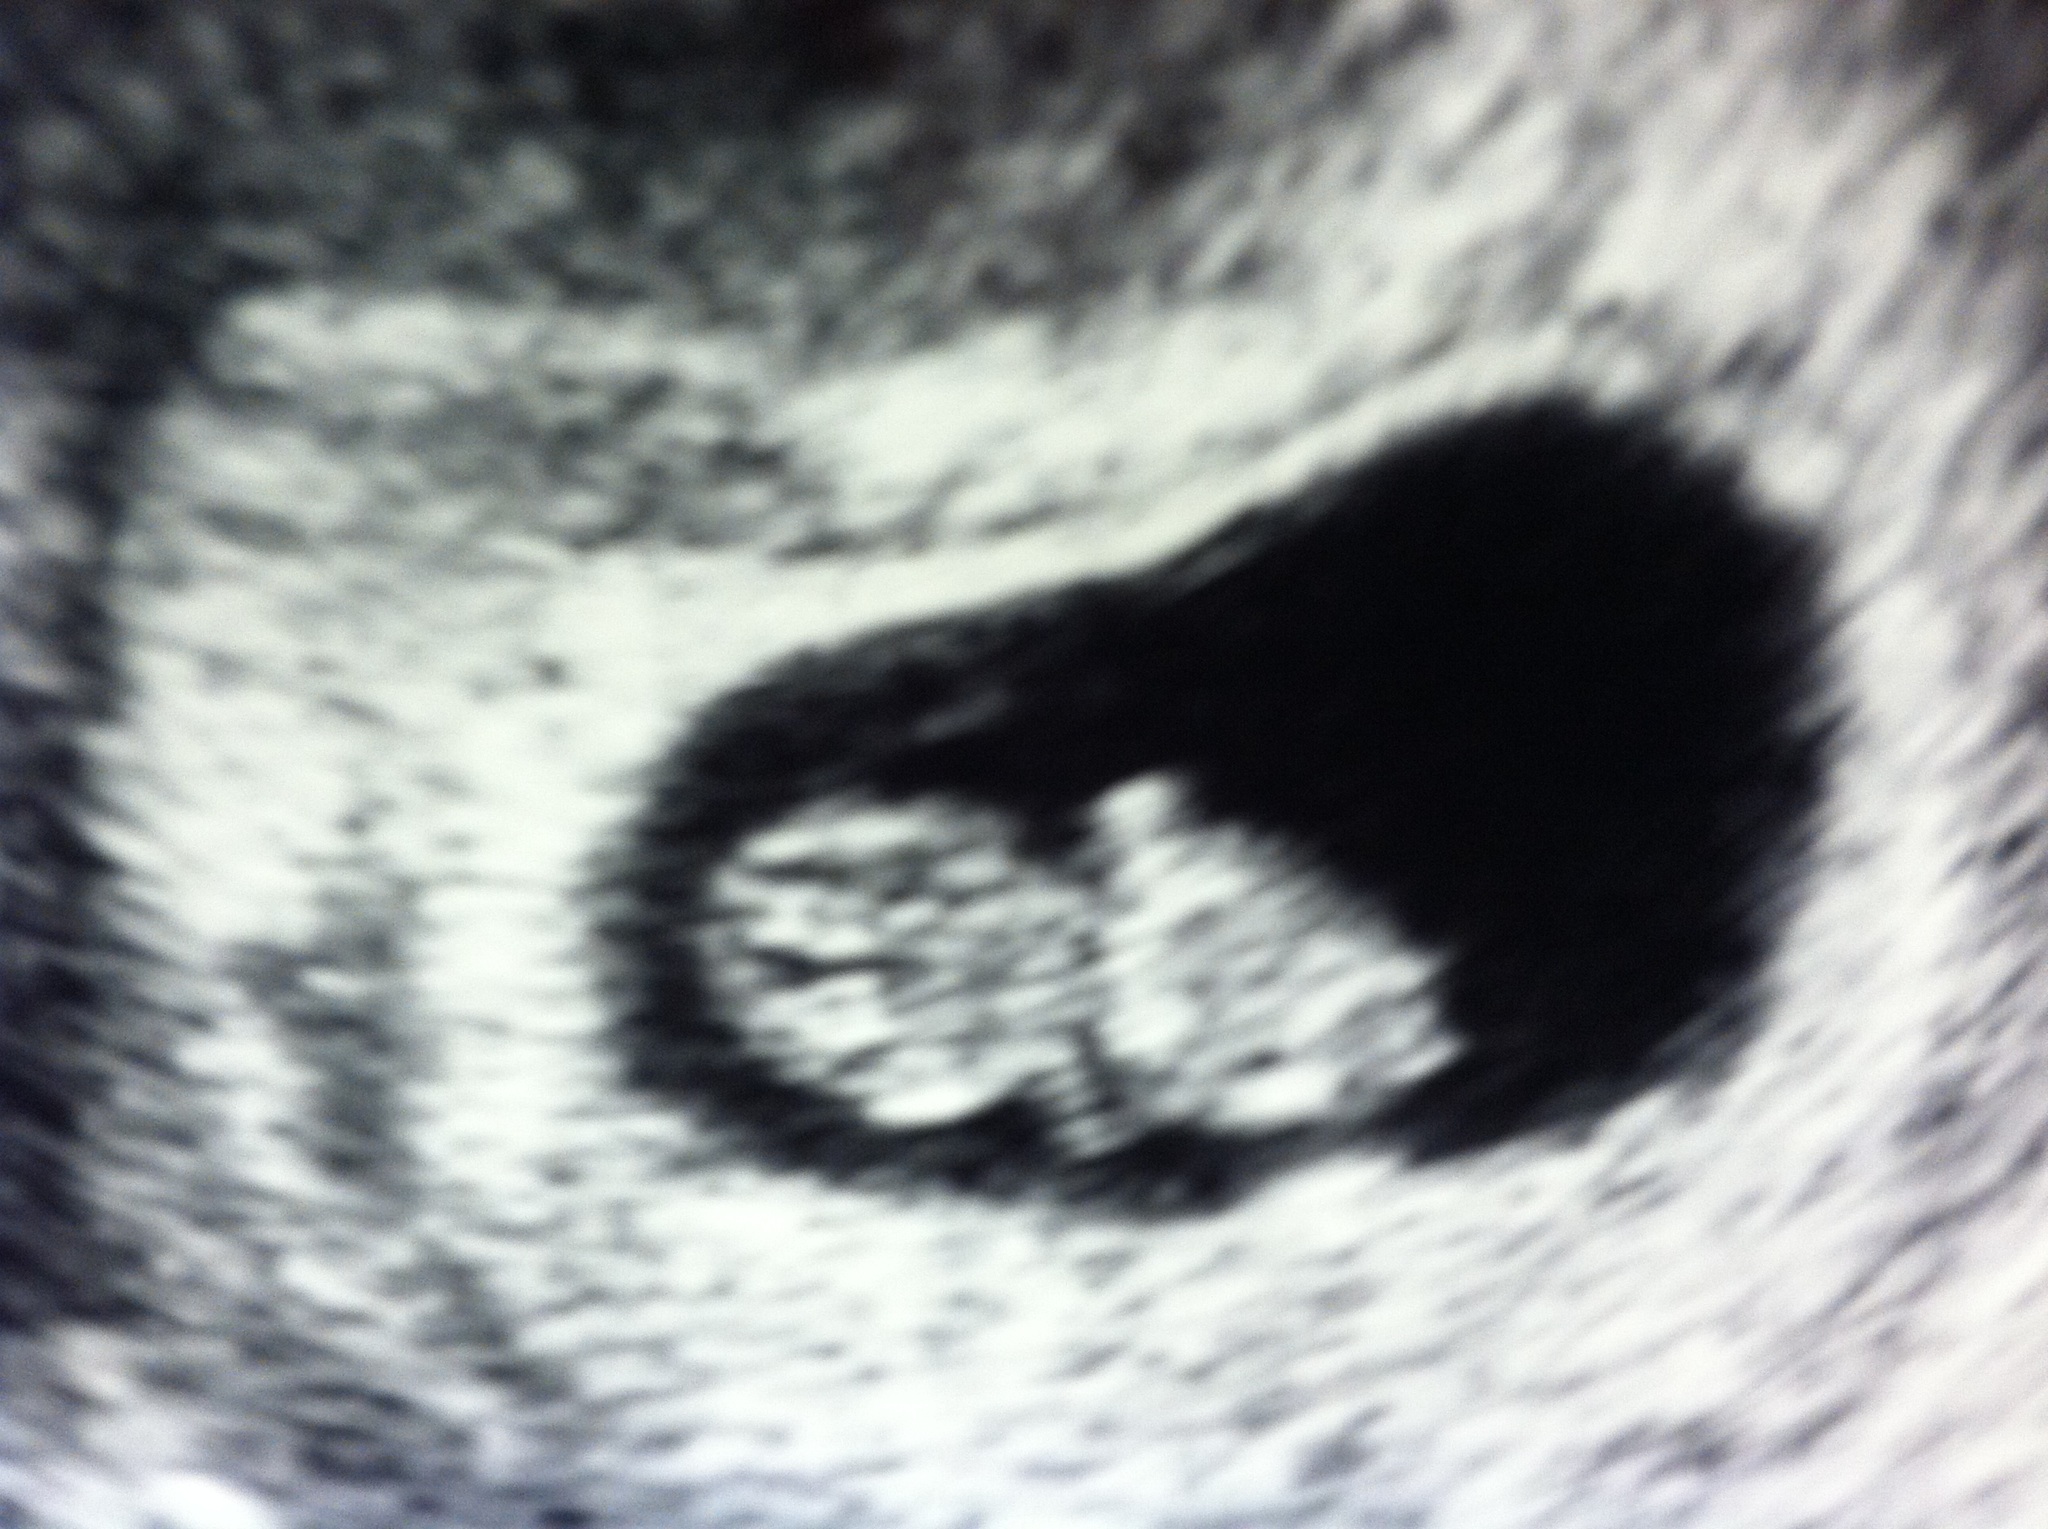

I can't tell where my placenta is located, but here are a few early ultrasound pictures :-) Attachment 8078Attachment 8079Attachment 8080

The first two look to be boy, the last looks SLIGHTLY more girl..

I agree with sunshiner. I was going to say the exact same thing. The thing is, it's possible the image was flipped at some point, and we don't know which one was a flipped image and which one wasn't. We can only go based on the assumption the picture wasn't flipped by the U/S tech (which you have no way of knowing unless you ask)

how accurate is this method?